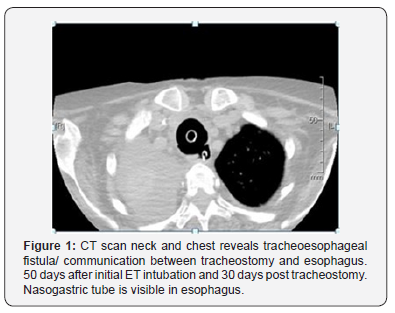

The air leak appeared again after 2 days (23 days post tracheostomy) and worsened to an extent that it was becoming difficult to maintain effective ventilation. Patient was also noticed to be developing significant abdominal distention, along with the air leak, required higher pressure settings for effective ventilation. A suspicion of Iatrogenic Tracheo-Esophageal Fistula was raised, and Thoracic surgery, Gastroenterology and Otolaryngology teams were consulted. The condition of the patient did not permit bronchoscopy and contrast swallow assessment so CT of neck and chest was organized. Overnight some bleeding was noticed from the oral cavity and tracheal stoma; this did not require any surgical intervention. The air leak worsened and became impossible to ventilate the patient. The tracheostomy tube was removed, and size 6 F cuffed endotracheal tube was inserted on 26 day post tracheostomy. CT scan of neck and chest (Figure 1) was performed and was highly suggestive of Tracheo-Esophageal fistula in the posterior wall of trachea. Unfortunately, the condition of the patient continued to deteriorate, and ventilation became progressively difficult. Endotracheal tube was changed again but with limited benefit. The patient expired 58 days after admission and 37 days post tracheostomy.

Patient’s medical file was reviewed retrospectively along with the radiological investigations. An interesting finding was noticed in the chest x-rays; there was a progressive increase in tracheal diameter at the site of tracheostomy tube cuff. These x-rays, shown in Figure 2, coincide with dates on which the air leak and progressive difficulty in mechanical ventilation was noticed.

The last chest x-ray (25 days post tracheostomy) shows a grossly distended tracheostomy tube cuff with a diameter of 50.13mm as compared to a diameter of 24.95 recorded 7 days post tracheostomy. On the 26th post tracheostomy day, patient could not be ventilated via tracheostomy tube due to unmanageable air leak and endotracheal tube was inserted. This proved effective as the cuff of endotracheal tube was positioned below the level of tracheostomy tube cuff and possible site of TEF. This progressive increase in the distension and diameter of tracheostomy tube cuff may be an important indicator of developing TEF. This finding has not been mentioned and used previously to predict and possibly prevent the development of TEF. We are reporting and mentioning the possible importance of progressive distension of tube cuff in relation to development of TEF for the first time in literature. Other investigations used in the diagnosis of TEF are bronchoscopy, esophagogram, esophagoscopy and echoendoscopic tracheobronchial examination [3,12], depending upon their availability and condition of the patient. In our patient, brochoscopy, considered as gold standard for diagnosis of TEF, could not be performed due to the rapidly deteriorating condition of our patient. C.T scan may also be helpful but only as an adjuvant investigation to confirm the clinical suspicion or diagnosis of TEF, but the diagnosis may be missed [16]. The condition of our patient allowed us to perform a CT scan only and this confirmed the suspicion of TEF.